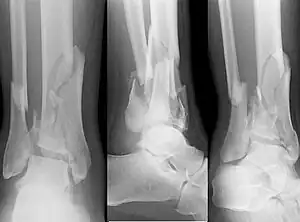

| X-ray of a fracture involving the articular surface of the Tibia | |

A pilon fracture, is a fracture of the distal part of the tibia, involving its articular surface at the ankle joint. Pilon fractures are caused by rotational or axial forces, mostly as a result of falls from a height or motor vehicle accidents. Pilon fractures are rare, comprising 3 to 10 percent of all fractures of the tibia and 1 percent of all lower extremity fractures, but they involve a large part of the weight-bearing surface of the tibia in the ankle joint. Because of this, they may be difficult to fixate and are historically associated with high rates of complications and poor outcome.[1][2][3][4]

Pilon fractures are categorized by two main X-ray schemes, Ruedi-Allgower classification system.[4] and Müller AO Classification of fractures.[5]